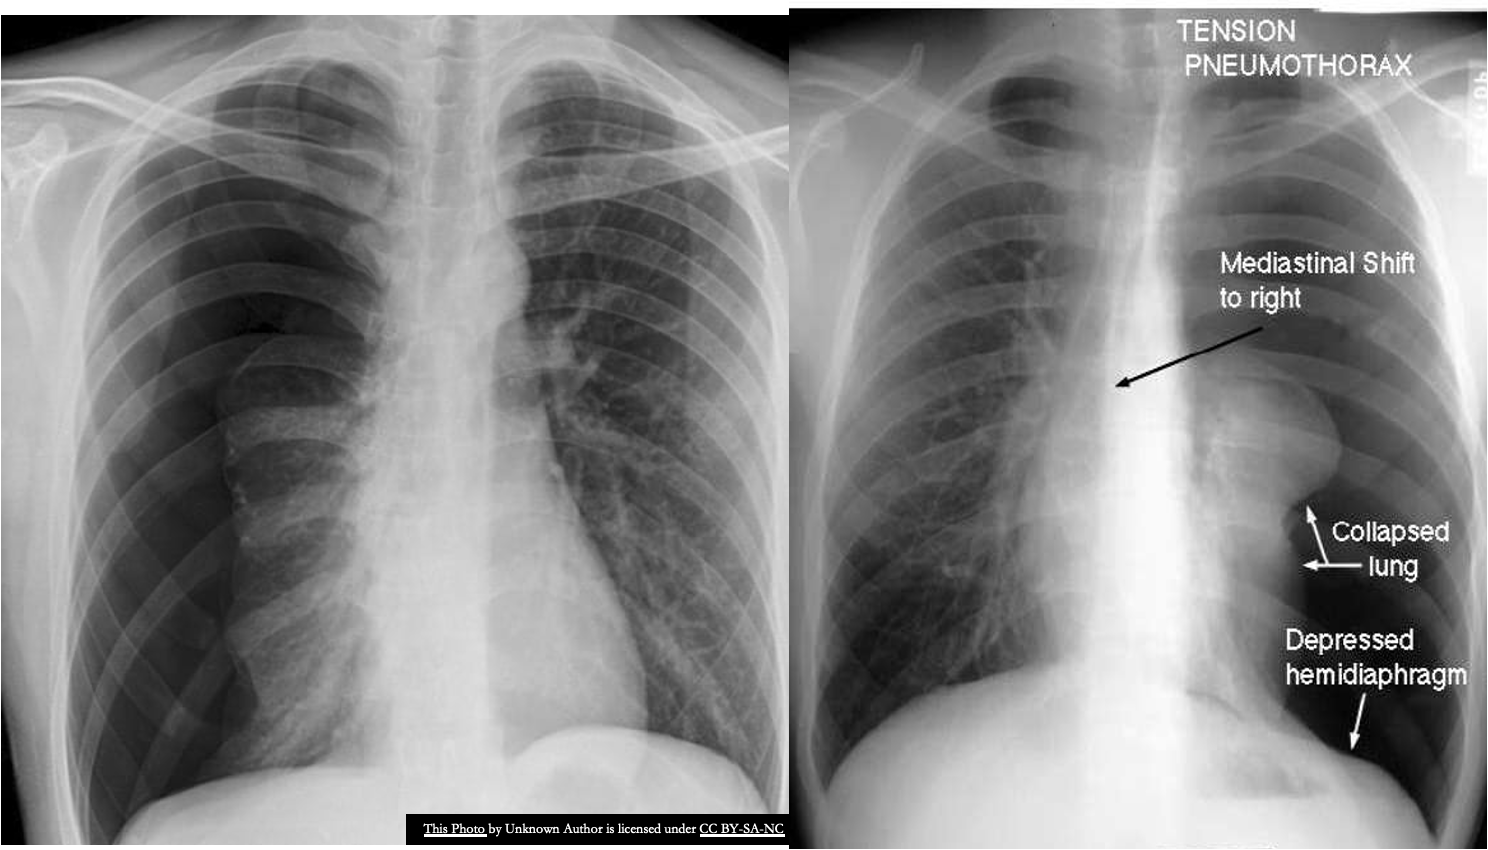

There are completely absent lung markings on the right, with the right lung collapsed and pushed across into the left hemithorax, along

with the mediastinal contents.

B) Supportive findings of Tension pneumothorax

- Ipsilateral diaphragmatic flattening/inversion and widened intercostal spaces.

- Mediastinal_shift toward the contralateral side.

- Tracheal_deviation toward the contralateral side.